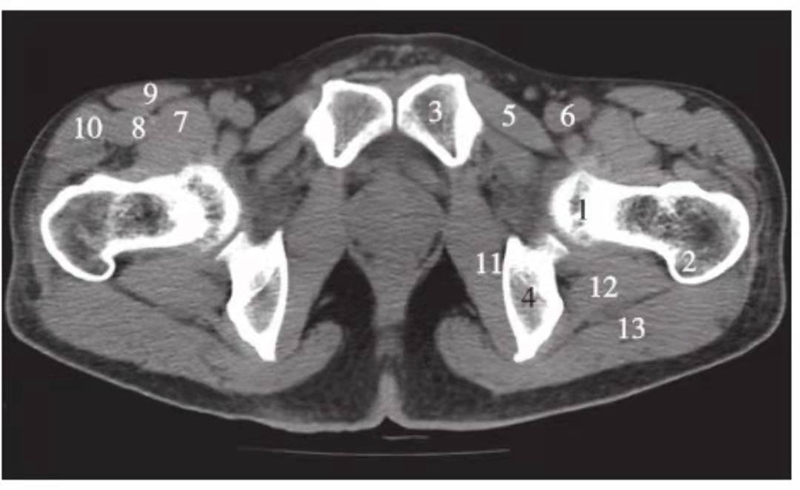

图3 股骨头凹层面(骨窗)

1.股骨头;2.星芒状结构;3.耻骨;4.坐骨;5.股骨头凹;6.髋臼窝;7.髋臼前唇;8.髋臼后唇